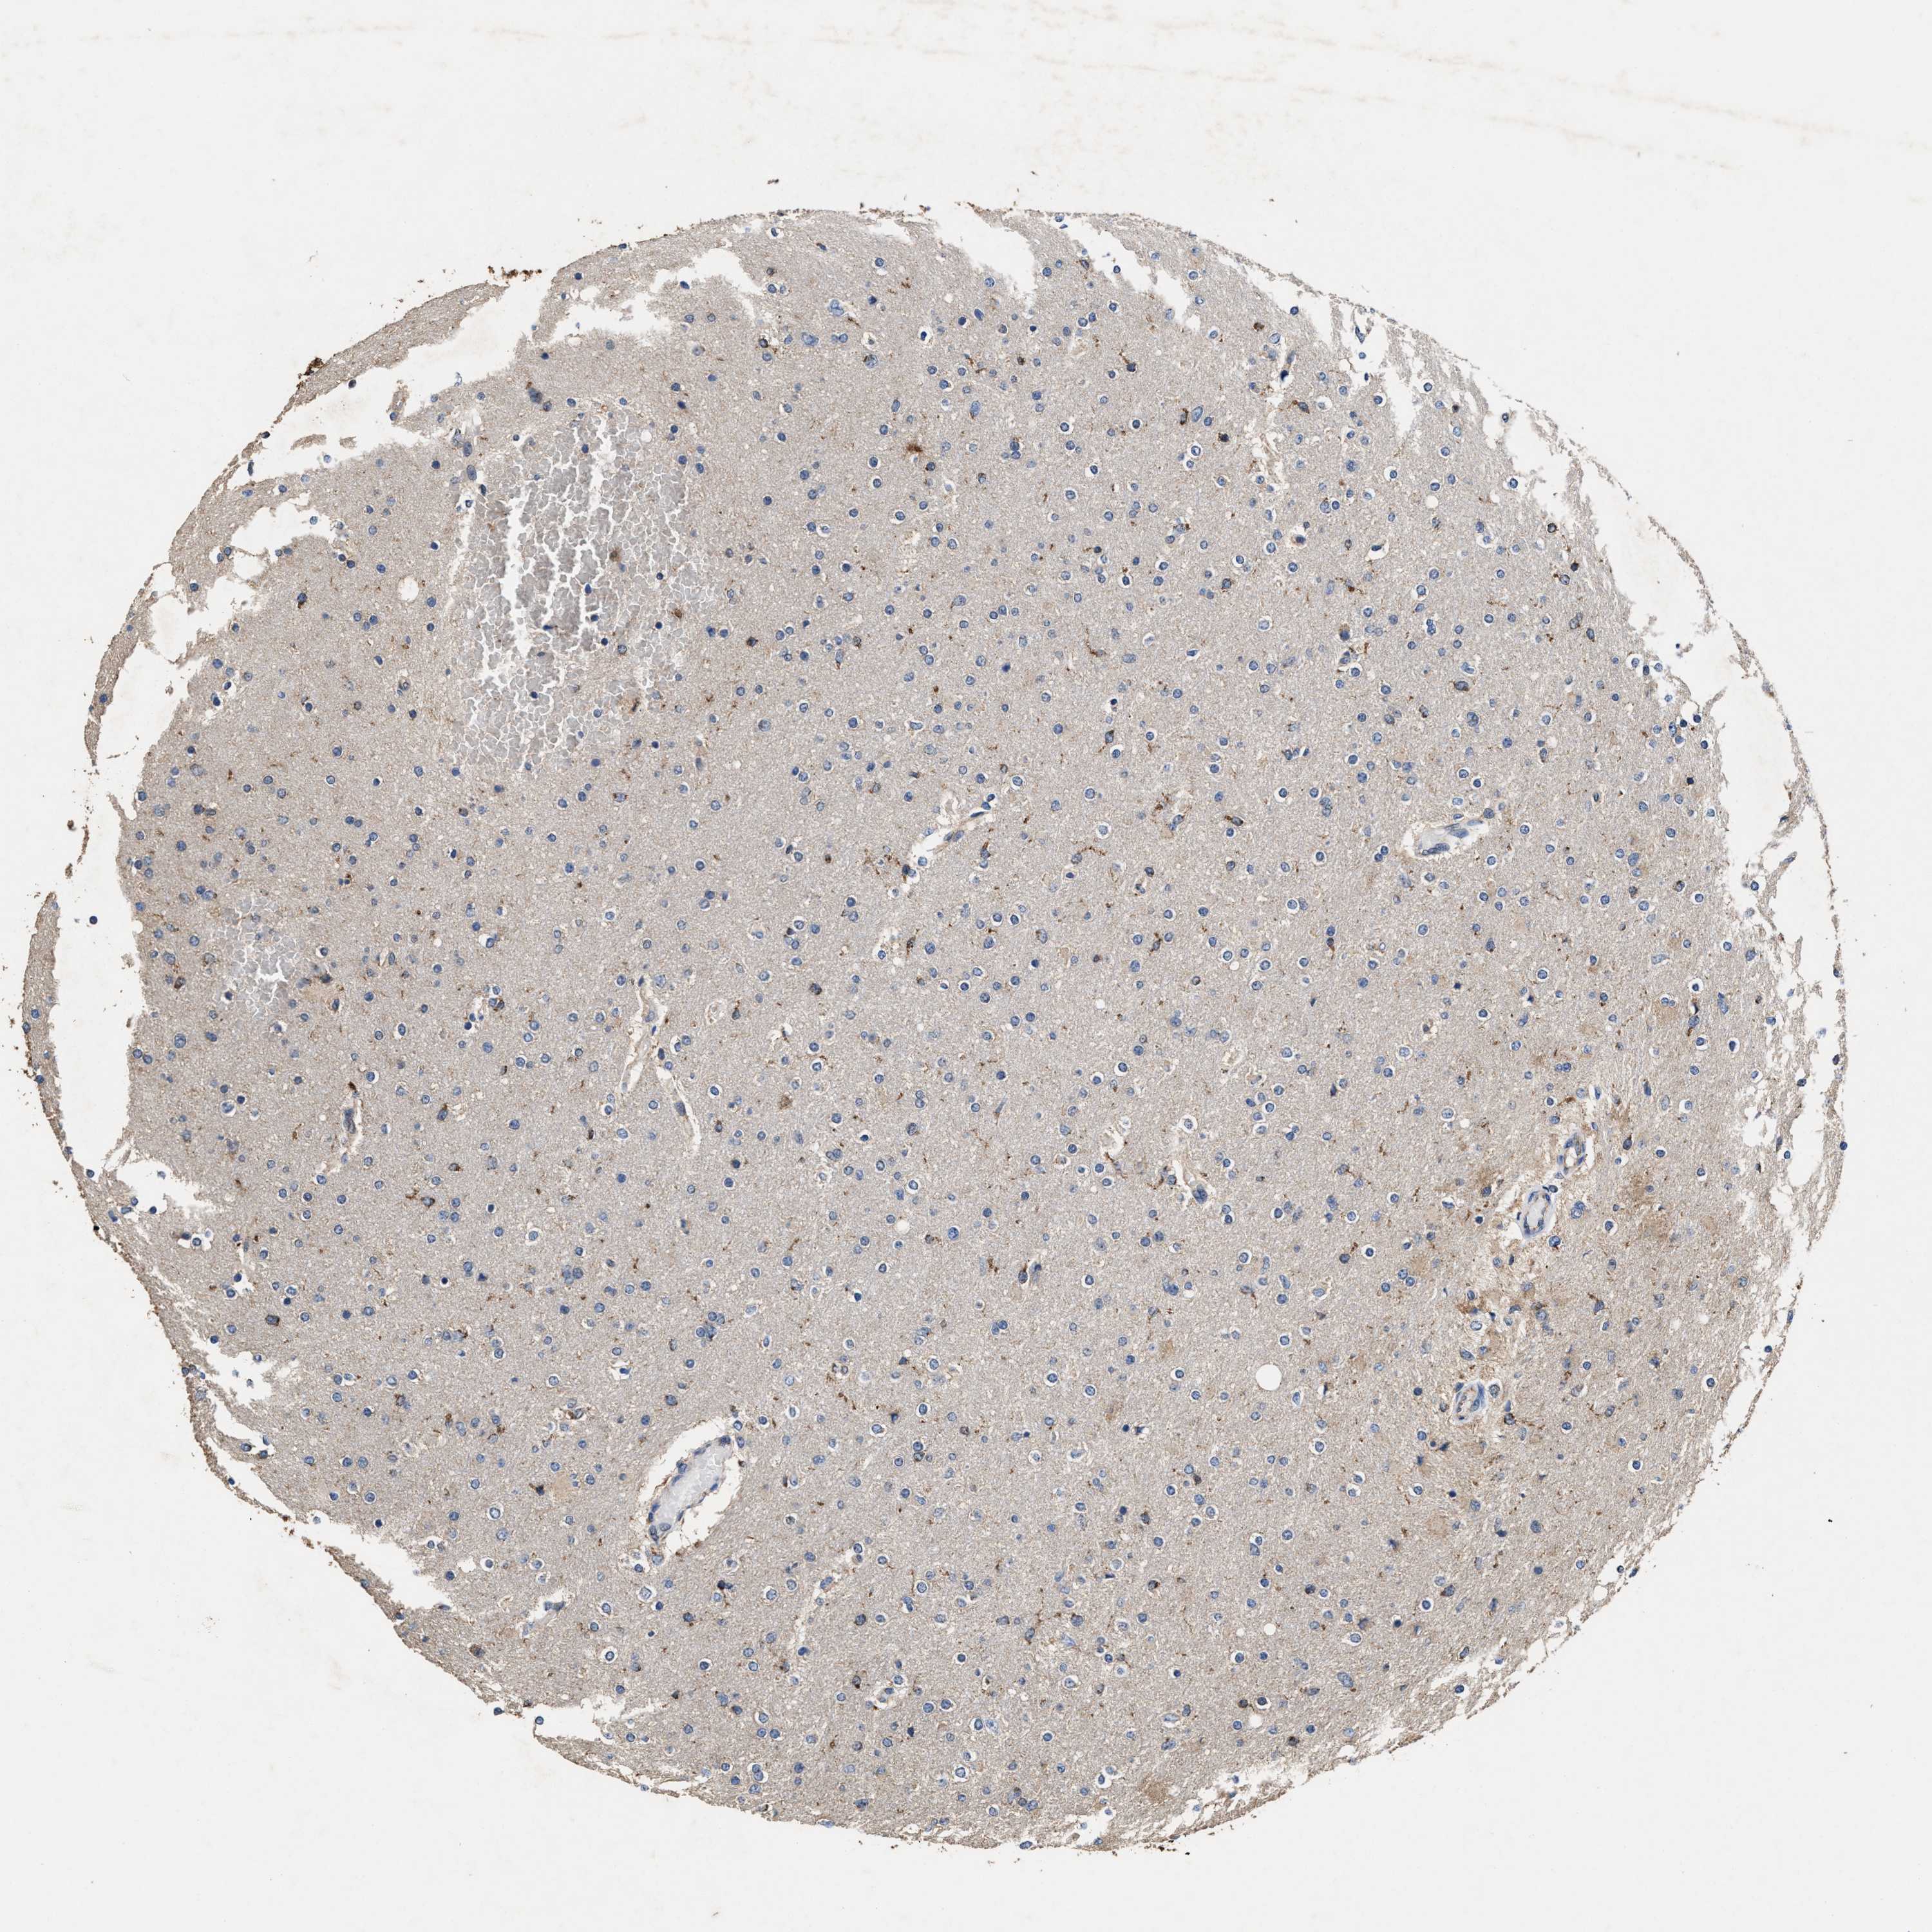

GLIOMA - Protein expressioni

A mouse-over function shows sample information and annotation data. Click on an image to view it in a full screen mode. Samples can be filtered based on level of antibody staining by selecting one or several of the following categories: high, medium, low and not detected. The assay and annotation is described here.

Note that samples used for immunohistochemistry by the Human Protein Atlas do not correspond to samples in the TCGA dataset.

Antibody stainingi

Antibody staining in the annotated cell types in the current human tissue is reported as not detected, low, medium, or high, based on conventional immunohistochemistry profiling in selected tissues. This score is based on the combination of the staining intensity and fraction of stained cells.

Each image is clickable and will lead to virtual microscopy that enables deeper exploration of all samples and also displays staining intensity scores, fraction scores and subcellular localization as well as patient and tissue information for each sample.

HPA022434

HPA022953

HPA022959

HPA028758

CAB007783

Glioma, malignant, High grade

Glioma, malignant, Low grade

Glioblastoma, NOS